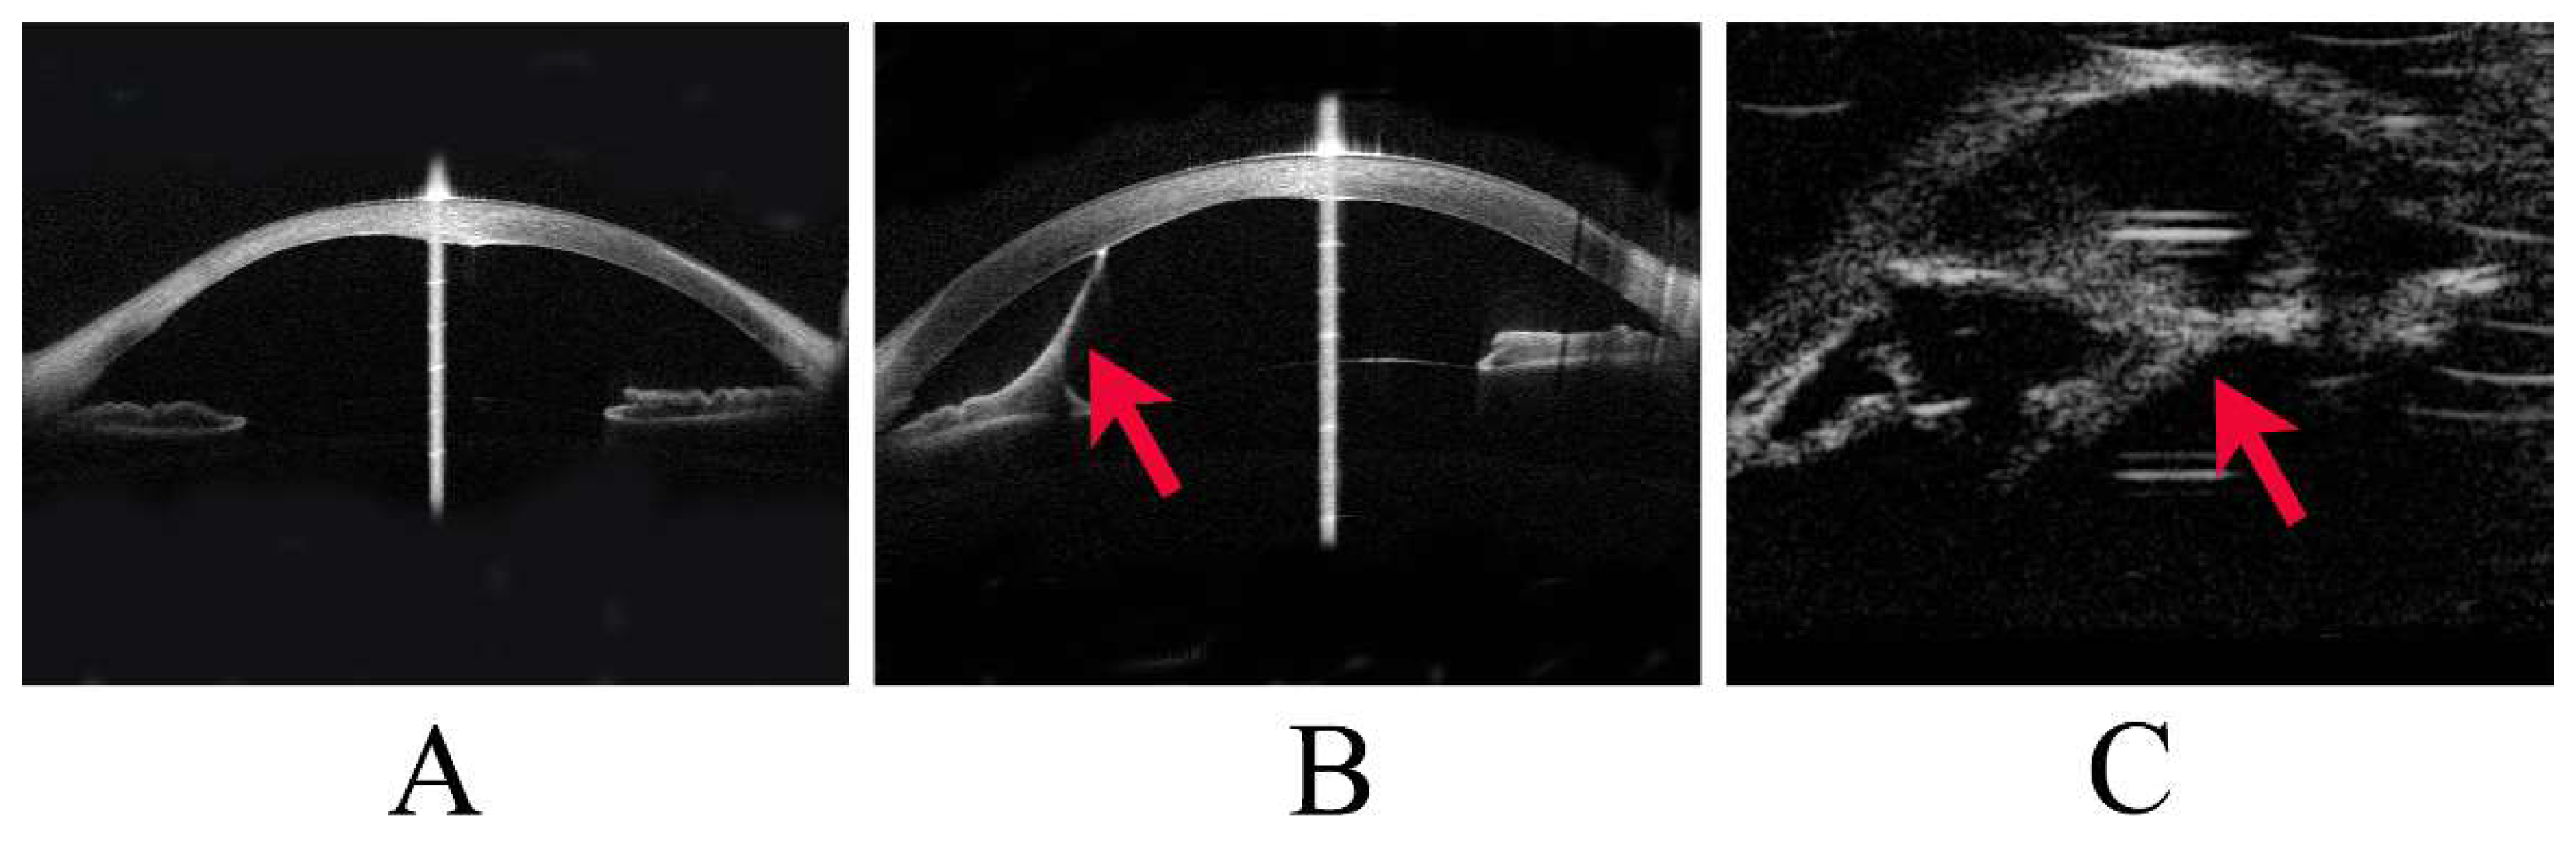

PA was diagnosed clinically and classified as Stages 1, 2, or 3 according to the severity of anterior segment dysgenesis. Stage 1 was defined as the presence of a posterior corneal defect only; Stage 2 as a posterior corneal defect with corneal iris adhesion; and Stage 3 as a posterior corneal defect with lens abnormalities, including lenticulocorneal adhesion (Figure 1). In addition, cases of PA with accompanying systemic disease were classified as Peters-plus syndrome. Corneal staphyloma referred to thinning of the cornea with a focal bulge.

This image shows representative cases of Stage 1 to Stage 3 Peters anomaly (PA).

(A) Stage 1 PA, with anterior segment optical coherence tomography (OCT) showing a posterior corneal defect.

(B) Stage 2 PA, with anterior segment OCT showing a strand (arrowhead) from the iris to the cornea and a posterior corneal defect.

(C) Stage 3 PA, with ultrasound biomicroscopy showing a strand (arrowhead) between the lens and the cornea.